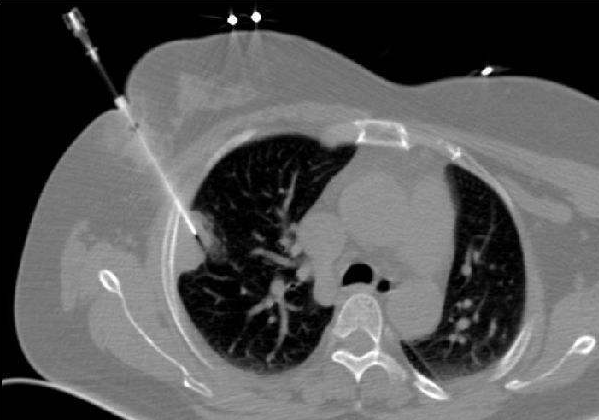

经皮穿刺肺活检(下文“穿刺”均为“经皮穿刺肺活检”)是在影像检查发现肺部有不能临床定性的异常物质时,在CT的引导下,用细针刺入病变局部,抽取部分细胞或组织,再将这些病变细胞或组织进行病理学检查来明确诊断。

而具体穿刺过程中,则会选择CT引导,让进针、取样、回收的全过程都可见。

最后整体将套管针拔出,这个过程中,套管针内部的活检组织始终和正常的肺部、胸膜、胸壁组织、皮肤没有接触,最大限度的避免肿瘤细胞在活检过程中局部脱落种植形成转移灶。